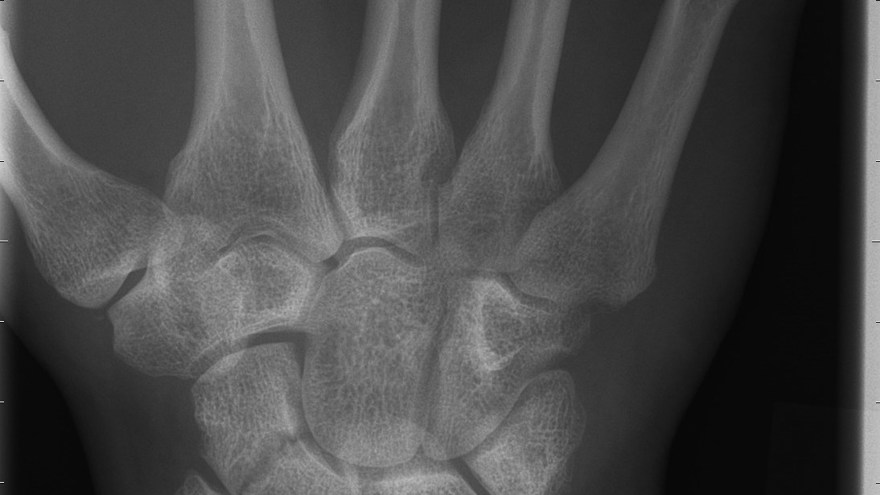

Scaphoideumfraktur

Symtom

Palpationsömhet i fossa Tabatiére, smärta vid axialt kompression av tummen samt vid dorsalextension respektive radialdeviation av handleden.

Drabbar ofta yngre individer i samband med sportutövning eller efter annat kraftigt dorsalextensionsvåld. Frakturen är ofta svår att identifiera på slätröntgen varför upprepade undersökningar och/eller CT/MR kan behövas.

Scaphoideum är dåligt vaskulariserad och ofta läker dessa frakturer (ffa proximala polfrakturer) långsamt; 3 månader i gips är normaltid! Gipsen skall immobilisera tumbas, handled och begränsa armens pro-supination. Utebliven läkning (pseudartros) är relativt vanligt och risken ökar om frakturen inte immobiliseras från skadetillfället.

Vid misstanke om scaphoideumfraktur (adekvat trauma, ömhet i fossa Tabatiére)

- Immobilisera i scaphoideumgips även om röntgen bedöms normal.

- Beställ då röntgenkontroll (utan gips) efter 10-14 dagar! Om röntgen är u a även efter 2 veckor, men status kvarstår: ordna snar MR- eller CT-undersökning!

Om skadan missas leder den mycket ofta till pseudartros och senare artros. En smärtsam pseudoartros kräver ofta att man tillför ben från crista illiaca vid operation och vid en handledsartros krävs någon typ av steloperation eller annat större ingrepp.

Det är tyvärr vanligt att frakturen missas då patienten kan uppleva symtomen som en distorsion, men det är också ganska vanligt att det missas av den undersökande doktorn. Detta sammantaget (s.k. 'patient's and doctors’ delay') innebär tyvärr att pseudoartrosoperationer är ganska vanliga.